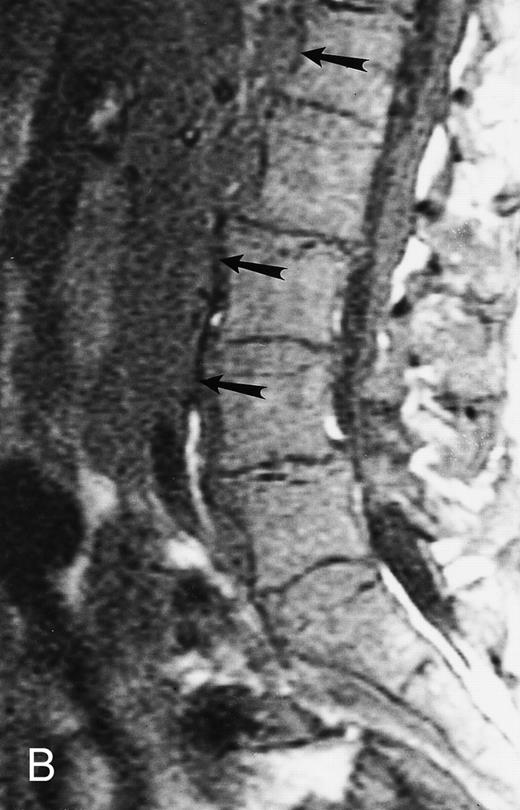

Focal MR pattern of abnormal marrow in a 48-year-old man with multiple myeloma: T1-weighted (500/10, TR/TE) (A), T2-weighted, fat-suppressed fast spin echo (5000/96, TR/TE, ET 16) (B), and enhanced T1-weighted (500/10, TR/TE) (C) sagittal MR images of the lumbar spine. Focal lesions (arrows) in L2 and S1 are dark in (A), bright in (B), and in (C) they enhance and become almost imperceptible from the uninvolved marrow.